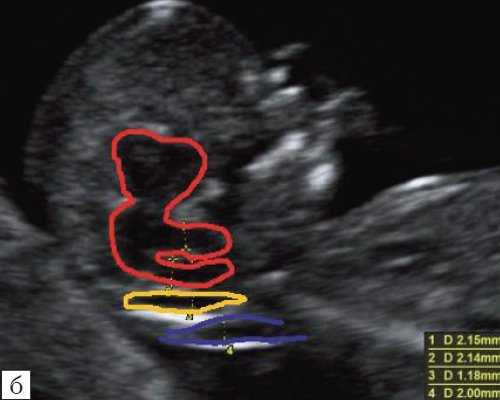

Особенностями визуализации этих структур является их гипо/анэхогенность. Так, при сроках 11-14 недель беременности таламус, ствол мозга, средний мозг выглядят практически анэхогенными. Итак, нормальная ультразвуковая анатомия этих структур головного мозга плода имеет следующие особенности: ствол и IV желудочек выглядят как анэхогенные продолговатые структуры, имеющие непосредственную близость (как бы выходящие) из диэнцефалона и среднего мозга. Все выше перечисленные анатомические структуры могут быть измерены и должно быть оценено их взаиморасположение (рис. 2, а).

б) Вид "осьминожки":

- красный цвет - диэнцефалон (таламус), со стволом мозга (верхняя ножка) и IV желудочком (нижняя ножка);

- желтый цвет - большая цистерна головного мозга;

- синий цвет - воротниковое пространство.

Особенности визуализации изложенных выше структур в данном сроке позволили нам выделить и назвать новый ультразвуковой маркер нормальной ультразвуковой анатомии мозга плода. Структуры головного мозга плода в этой области схожи с осьминогом, у которого есть голова и две приблизительно равновеликие по диаметру ножки, представляющие собой ствол мозга и IV желудочек. Ниже ножек "осьминожки" визуализируется 2 "подушки осьминожки" - это два анэхогенных пространства - большая цистерна и воротниковое пространство (рис. 2, б).

Так как речь идет о сроках первого скрининга, т.е. раннего осмотра, новый ультразвуковой маркер мы назвали "осьминожкой" (рис. 3).

а) Стрелками указана голова "осьминожки" - диэнцефалон (таламус).

б) Красный цвет - диэнцефалон (таламус), со стволом мозга (верхняя ножка) и IV желудочком (нижняя ножка); желтый цвет - большая цистерна головного мозга; синий цвет - воротниковое пространство.

Как сказано выше, имеет значение и измерение ножек "осьминожки", так среднее значение диаметра нижней ножки, т.е. IV желудочка в зависимости от КТР в срок 11-14 недель варьирует от 1,5 до 2,5 мм (рис. 4).

Рис. 4. Измерение и взаимоотношение ножек "осьминожки" - ствола мозга и IV желудочка у плода, беременность 12 недель.

Измерение ножек "осьминожки".

Красный цвет - диэнцефалон (таламус), со стволом мозга (верхняя ножка) и IV желудочком (нижняя ножка); желтый цвет - большая цистерна головного мозга; синий цвет - воротниковое пространство.